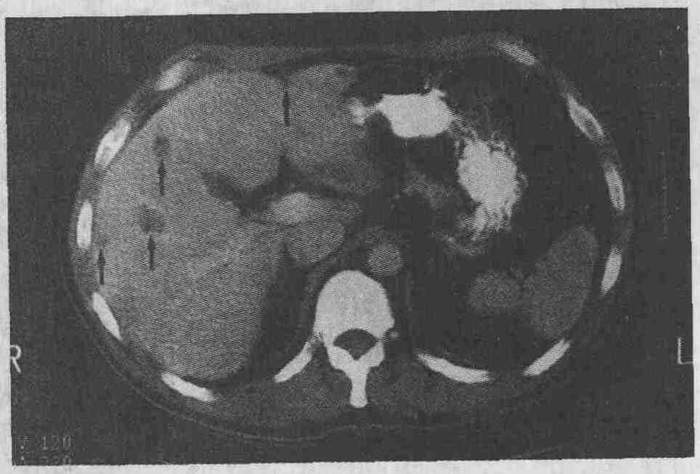

Выявить очаговые нарушения в паренхиме печени можно с помощью эхографии. В результате этой процедуры определяется плотность паренхимы и очаги поражения, подразделенные на участки со слабой, смешанной, сильной эхоструктурой, или ее полным отсутствием.

Очаговые поражения могут быть множественными, сливающимися и единичными. При ухудшении состояния пациента наблюдаются изменения эхогенности пораженного участка.

Эхография также позволяет определить развитие многочисленных или единичных случаев кальцификата в паренхиме, т.е. уплотнений. У ребенка они возникают реже, чем у взрослых.

Очаги поражения, эхоструктура которых не была выявлена — это паренхиматозные кисты. С помощью эхограммы определить их можно только при достижении 3-5 мм в диаметре. Кистообразные образования подразделяются на несколько видов, отличающихся причиной их развития (приобретенная или врожденная) и способами появления (паразитарные, непаразитарные, ложные и истинные).

Диффузные изменения – это острый и хронический гепатит, цирроз, жировые накопления и другие нарушения структуры из-за болезней. При гепатите у человека увеличиваются размеры печени, но ее структура при этом остается без изменений.

Нарушения поверхности паренхимы возникают, если воспаление начинает расти. В этом случае утолщается тонкая стенка печени. При проведении эхографии определяется низкая эхогенность органа, но наоборот возросшая звукопроводимость.

При наличии гепатита невыраженные воспаления в паренхиме становятся причиной неоднородного уровня эхогенности. Если у пациента диагностирован цирроз, то очаги поражения с нарушенной эхогенностью начинают расти в количестве, потому как гомогенная структура печени быстро разрушается.

Параметры таких очагов могут составлять 0,5-2 см. Структура паренхимы становится неоднородной в результате нарушения обмена веществ, желчных застоев и жировых перерождений.